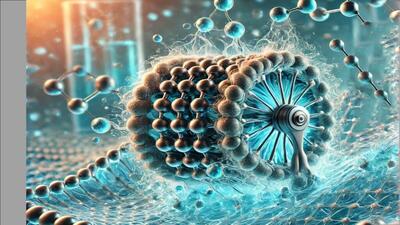

تشخیص بیماری با یک مولکول

حسگرهای جدید نانوپور قادرند با شناسایی مولکولهای منفرد، بیماریها را سریعتر و دقیقتر از همیشه تشخیص دهند.